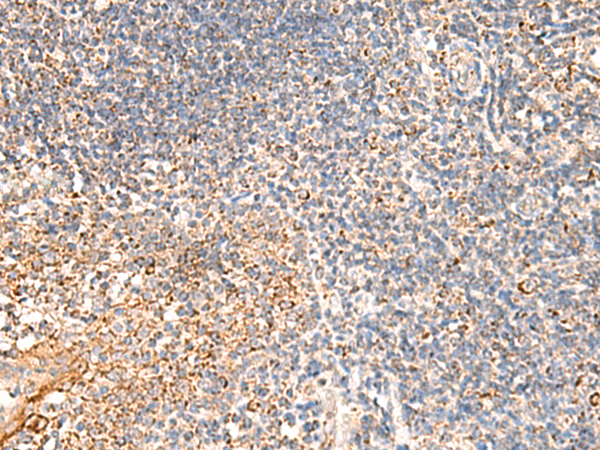

分类: 科研抗体货号: P10118别名: QA1; HLA-6.2应用: IHC反应种属: Human